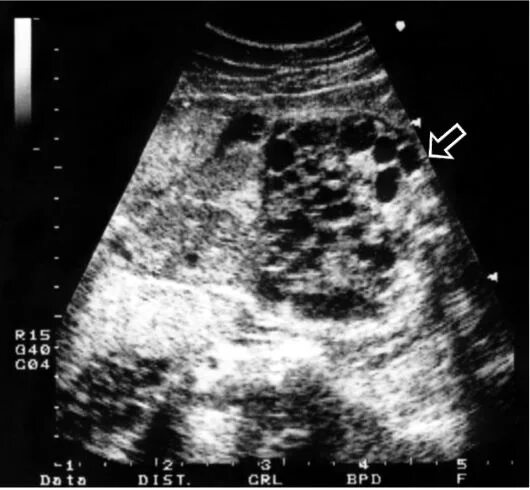

Узи аномалий